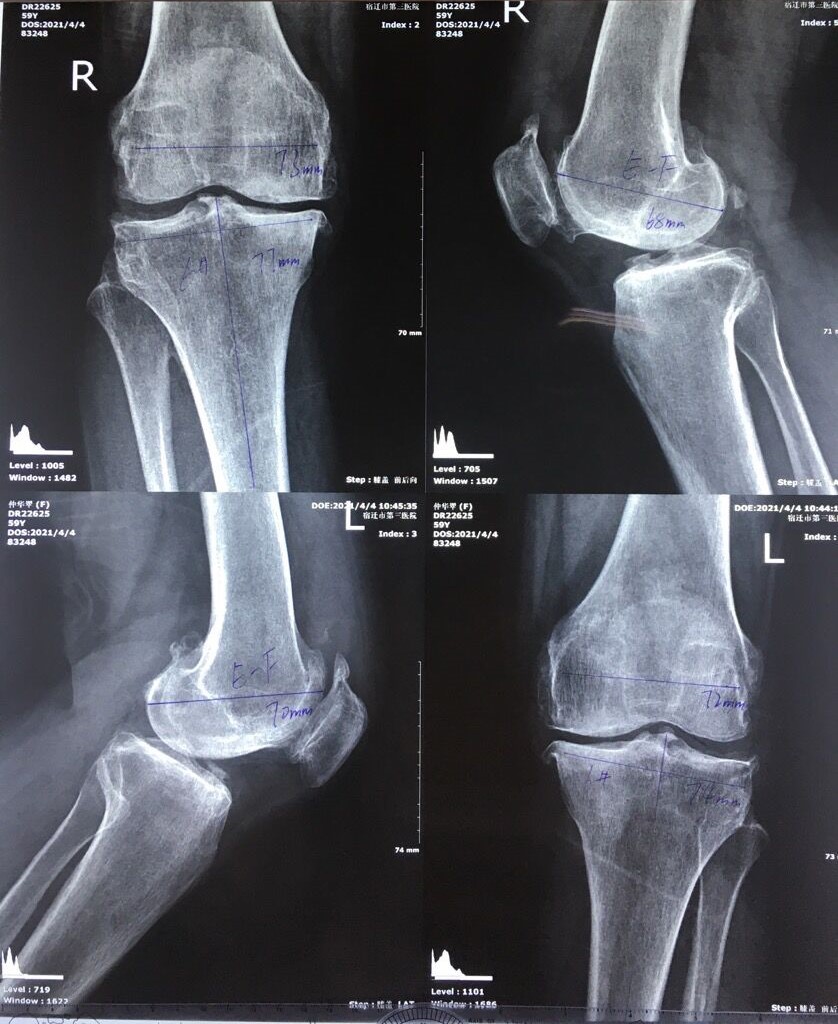

61歲的仲女士雙膝關(guān)節(jié)疼痛達(dá)10年之久,近年,病情不斷惡化,雙膝關(guān)節(jié)疼痛加重,雙下肢明顯呈O形,跛行了近3年,行走時(shí)伴有劇烈疼痛,平時(shí)活動(dòng)受到很大的限制,為此四處求醫(yī),但疼痛依然如影隨形,未能減輕。

2020年末,看到之前和自己同樣腿疼不好走路的鄰居,不但走起路來(lái)輕松自如,不像之前那樣蹣跚,而且還可以在家做事了!便趕忙前去詢問(wèn),得知其在宿遷市第三院通過(guò)關(guān)節(jié)置換手術(shù),治好了伴隨多年的關(guān)節(jié)疾病,趕緊詳細(xì)詢問(wèn)醫(yī)院情況,當(dāng)即要來(lái)聯(lián)系電話、地址,仲女士并把這一好消息告訴同樣深受腿疼折磨的鄰居好友栗女士,她們倆相約一起來(lái)到我院骨科就診。經(jīng)過(guò)脊柱關(guān)節(jié)團(tuán)隊(duì)專家的詳細(xì)檢查、評(píng)估,兩人均被確診為雙側(cè)膝骨性關(guān)節(jié)炎。由于我院關(guān)節(jié)置換手術(shù)需要排隊(duì)預(yù)約,她們當(dāng)即交錢(qián)預(yù)約排隊(duì),被告知四月份會(huì)提前電話通知過(guò)來(lái)辦理入院手續(xù)。兩人滿心期待的回家了!

4月4號(hào)倆人按照預(yù)約一同到院辦理入院手續(xù)。入院后,醫(yī)護(hù)人員按照關(guān)節(jié)置換圍手術(shù)期管理流程,對(duì)她們的身體狀況做了詳細(xì)檢查并進(jìn)行了綜合評(píng)估,最后制定出了周密的手術(shù)方案。